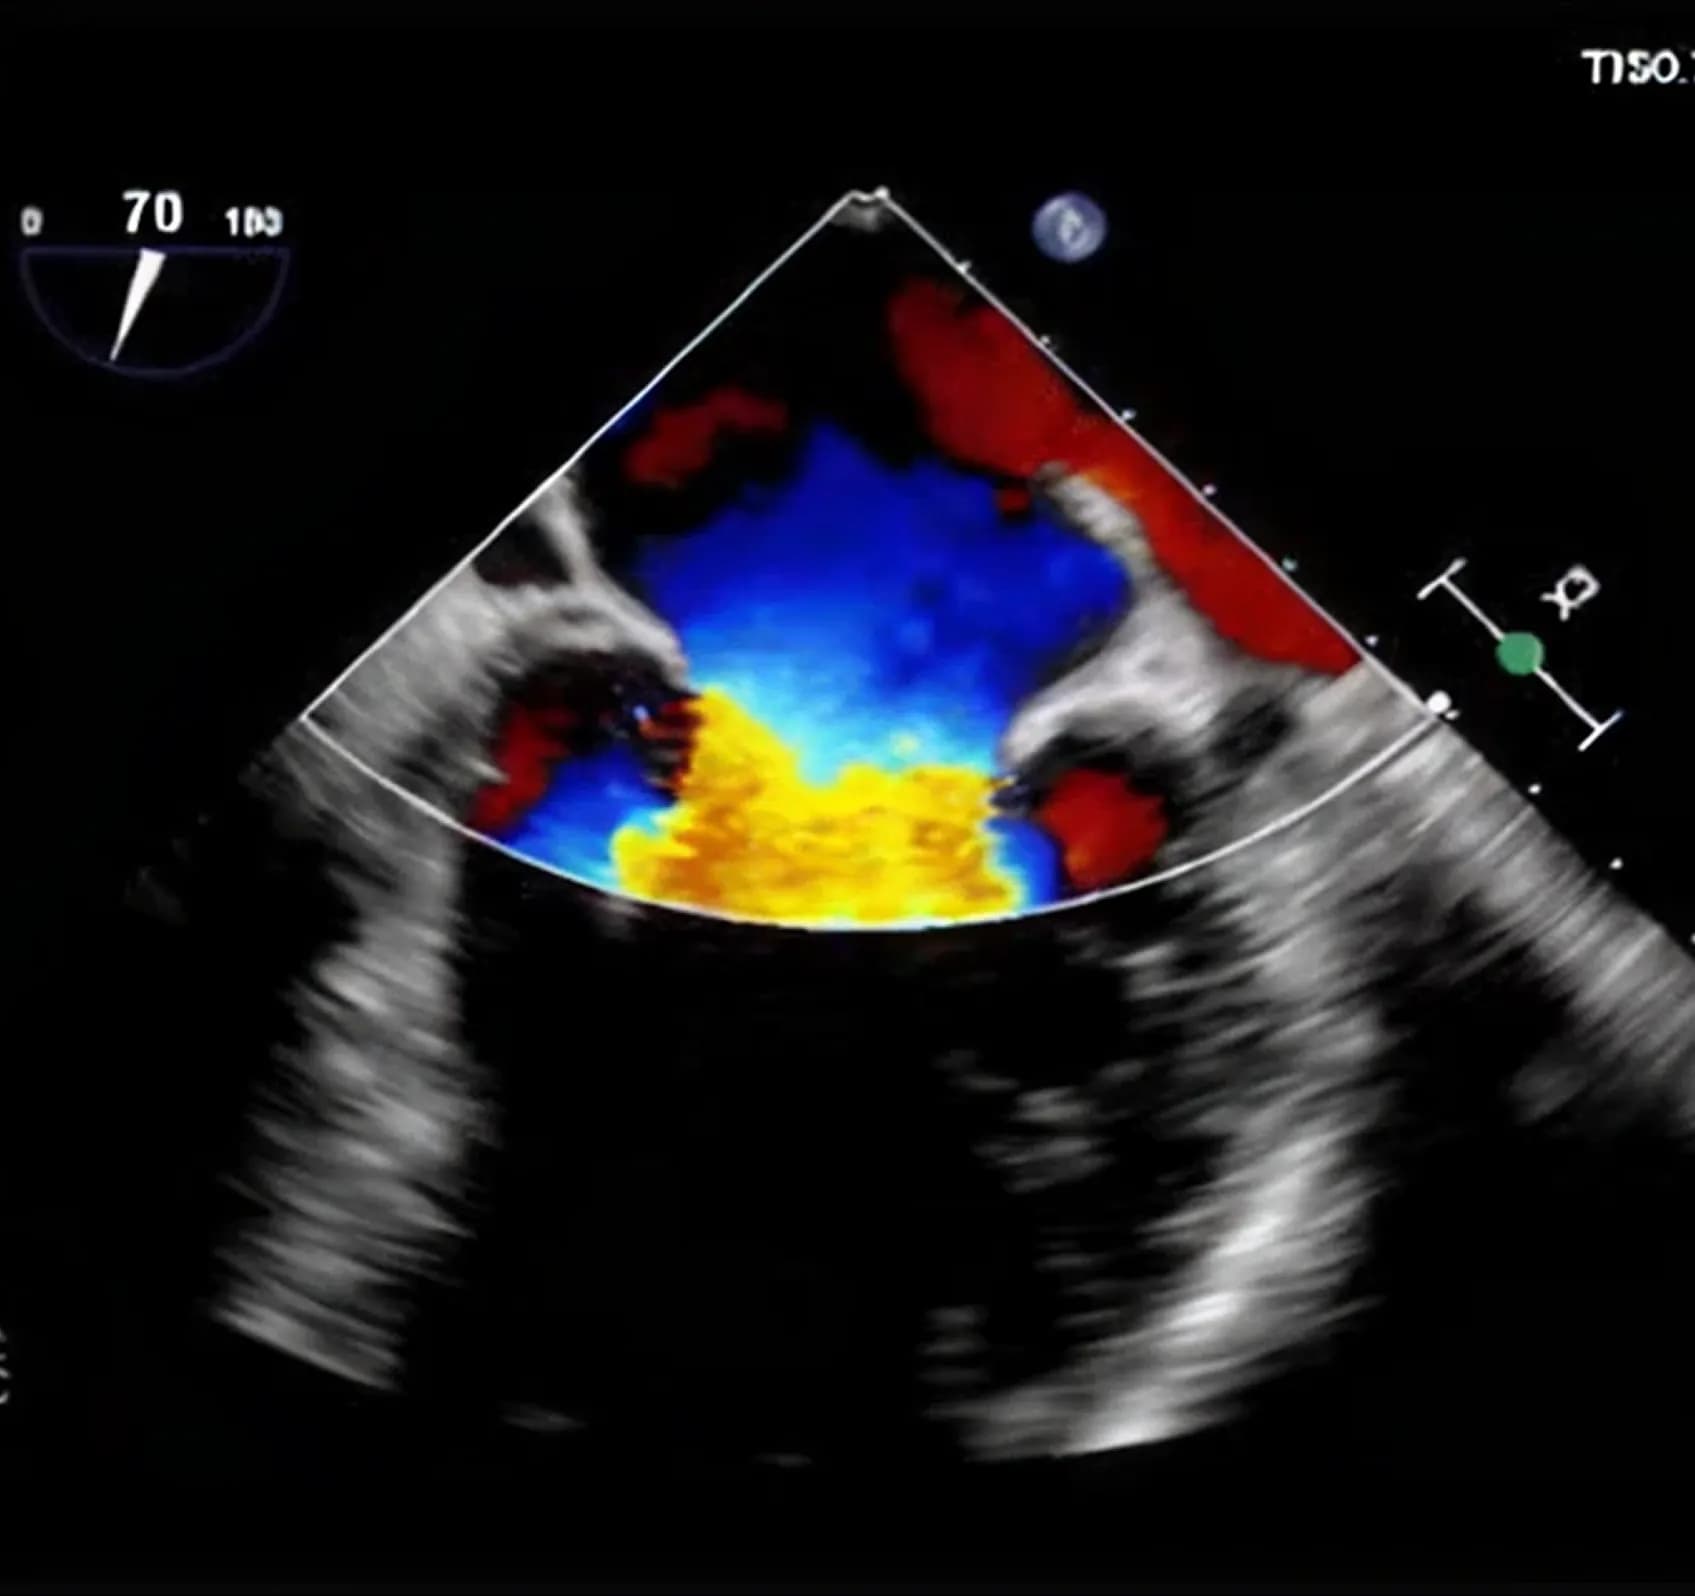

- Echocardiography